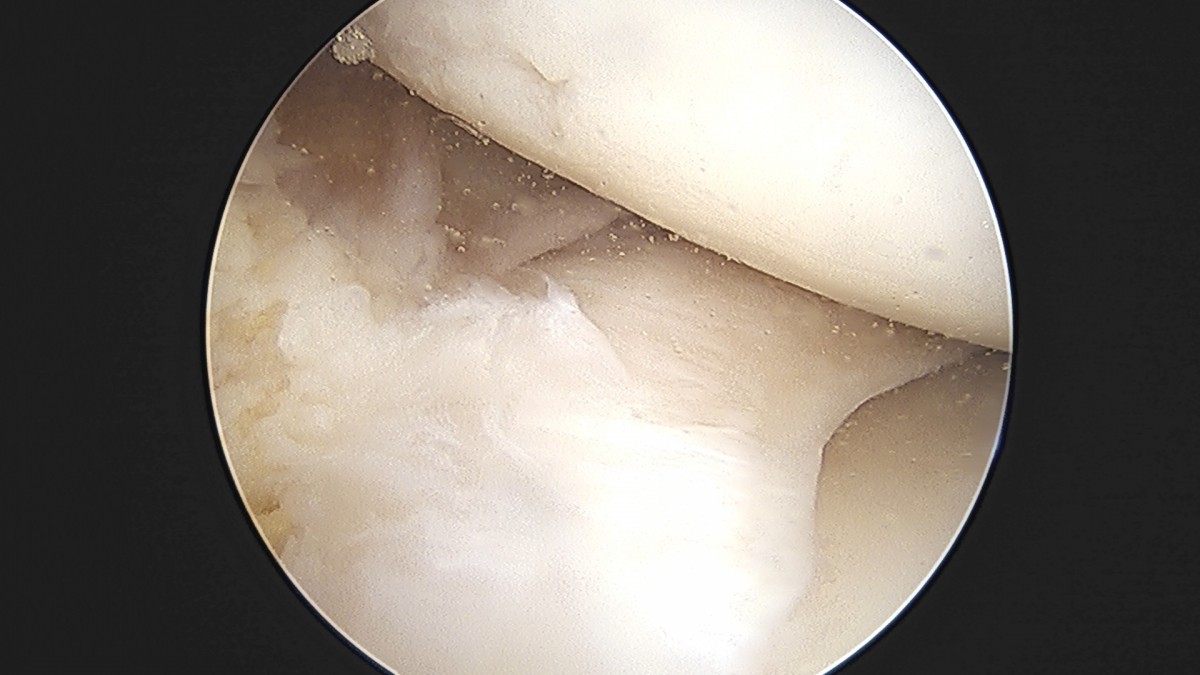

이재상원장님 무릎 낭종 제거술 김은O 환자

작성자 최고관리자 댓글 0건 조회 789회 작성일 25-09-16 15:20